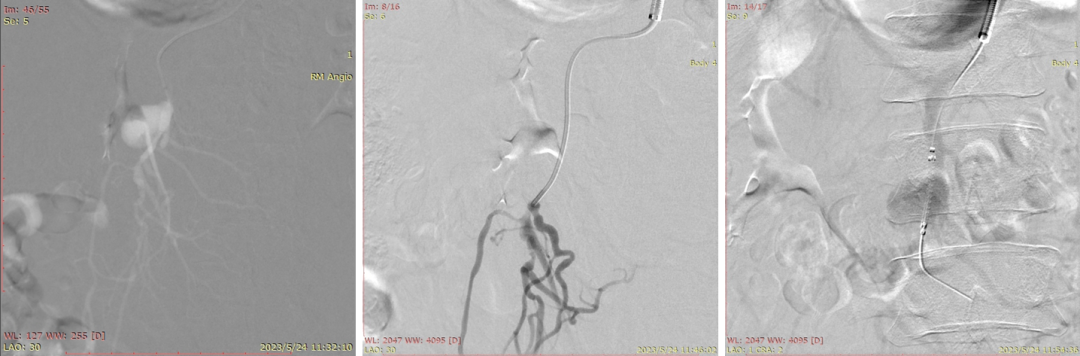

20230524DSA夹层动脉瘤

20230524DSA:VB支架植入

20230524DSA:仍有造影剂进入假腔

20230524DSA:再次送入VB